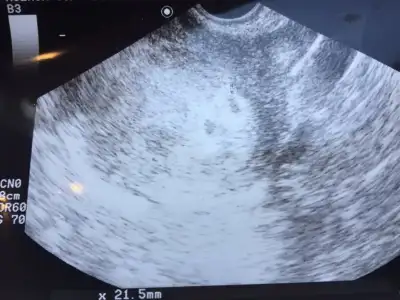

Kızlar dün kontrole gittim kese görmek için iki embriyo transferi yapmıştım ikisi de tutmuş

biri diğerinden küçük görünüyor ama korkacak birsey yok günden güne değişir dedi doktor çok mutluyum ayın 4ünde kalp atışı duymaya gideceğim Allah sizlere de nasip etsin inşallah

biri diğerinden küçük görünüyor ama korkacak birsey yok günden güne değişir dedi doktor çok mutluyum ayın 4ünde kalp atışı duymaya gideceğim Allah sizlere de nasip etsin inşallah

İkiz mi yaniiiiiiKızlar dün kontrole gittim kese görmek için iki embriyo transferi yapmıştım ikisi de tutmuşbiri diğerinden küçük görünüyor ama korkacak birsey yok günden güne değişir dedi doktor çok mutluyum ayın 4ünde kalp atışı duymaya gideceğim Allah sizlere de nasip etsin inşallah

Ayyyy çok güzel yaaa maşallah maşallahEvet ikiz bebişlerim oluyor